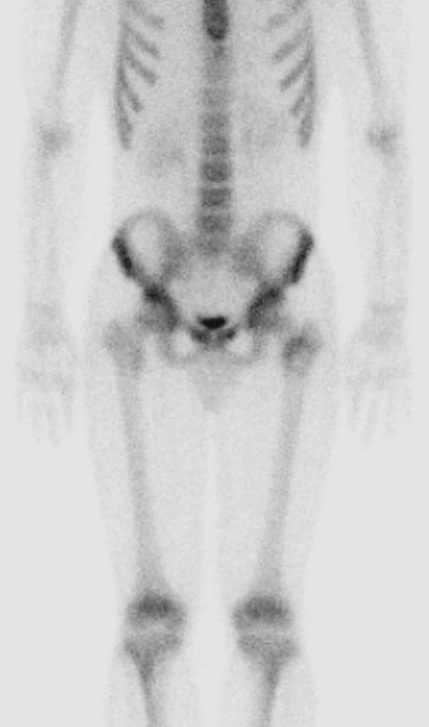

Figure 1 for case fibrous dysplasia ( RID3738 )

Figure 1